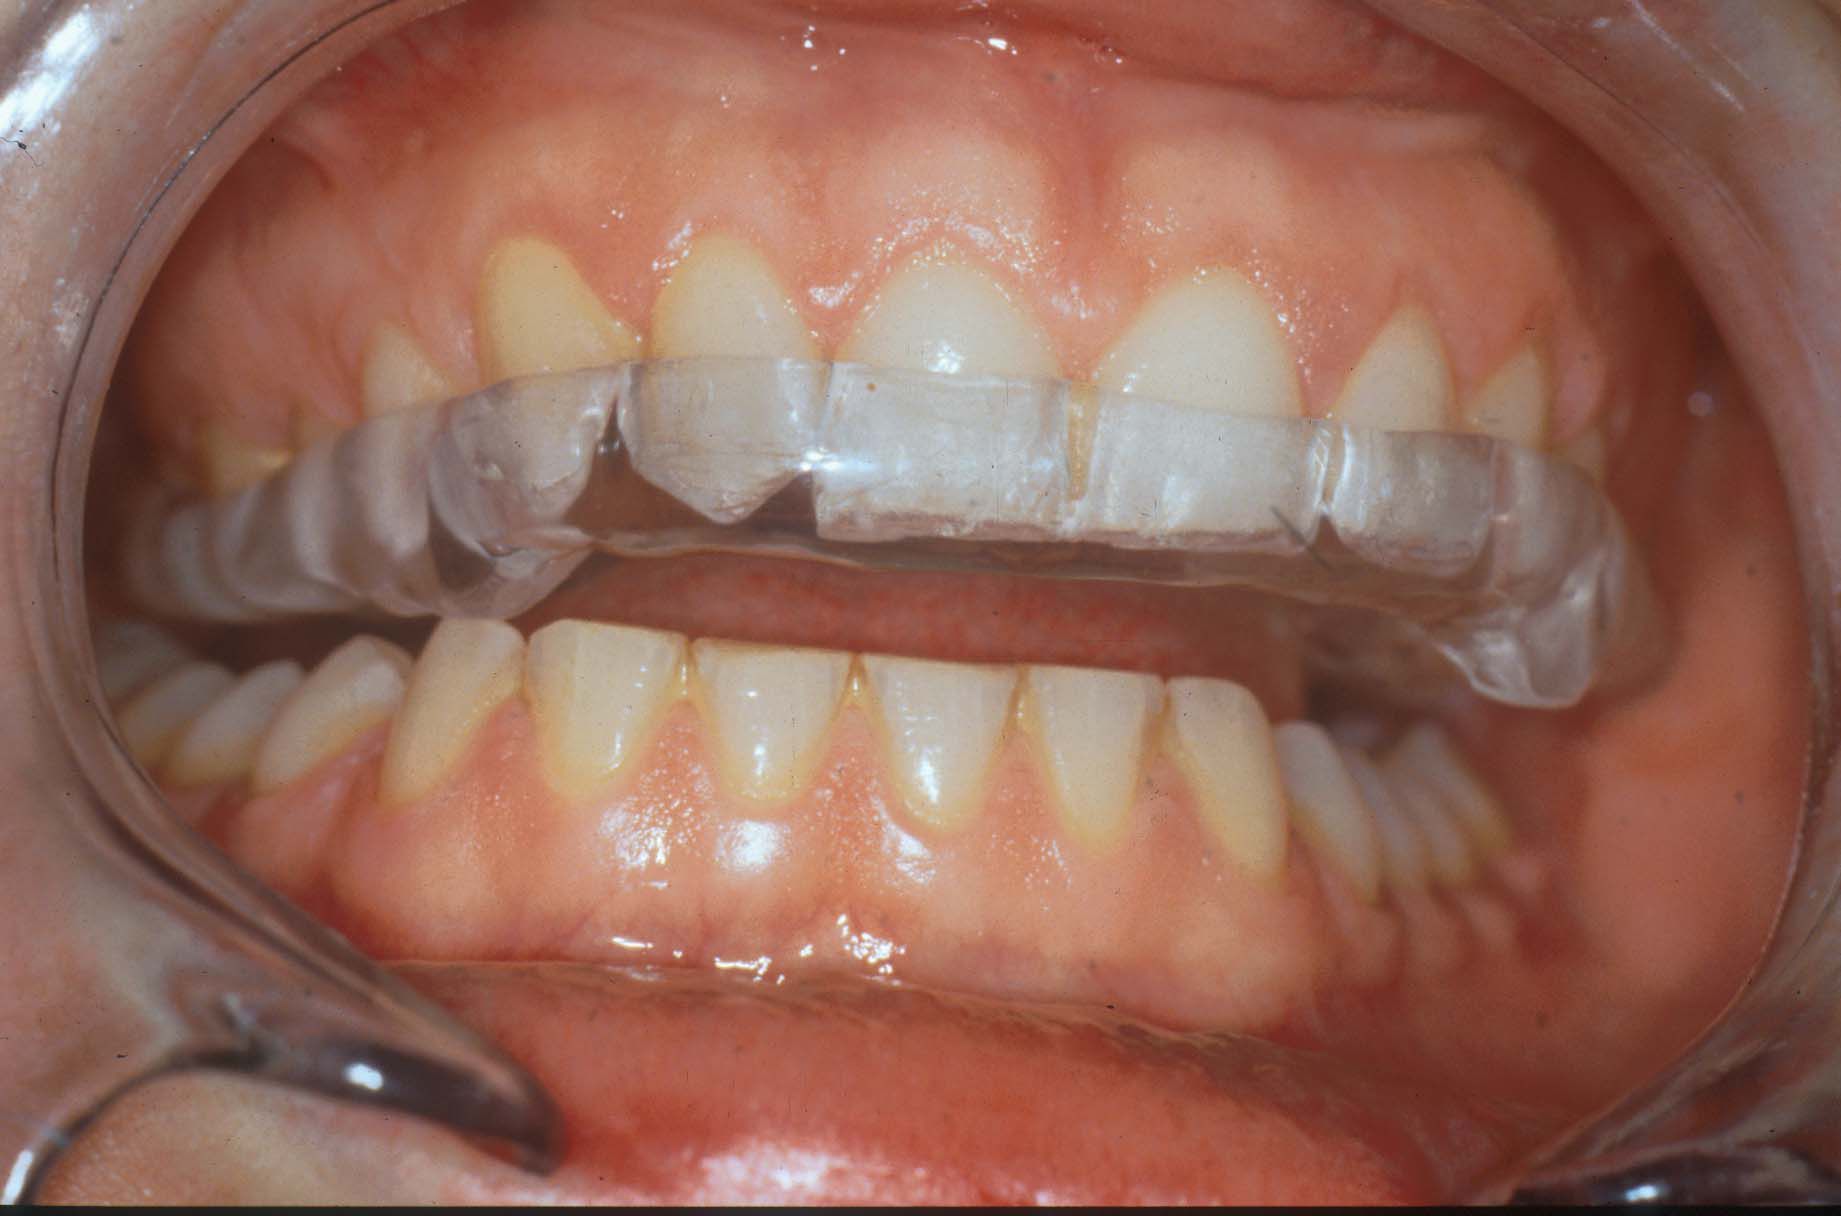

La Férula Oclusal

Las férulas u ortosis oclusales son uno de los recursos más comunes y efectivos para el tratamiento de los trastornos temporomandibulares y del bruxismo, pero siempre requieren un diseño adecuado y personalizado bajo la supervisión de un dentista, así como ser sometidas a revisiones y ajustes periódicos para su correcto funcionamiento.